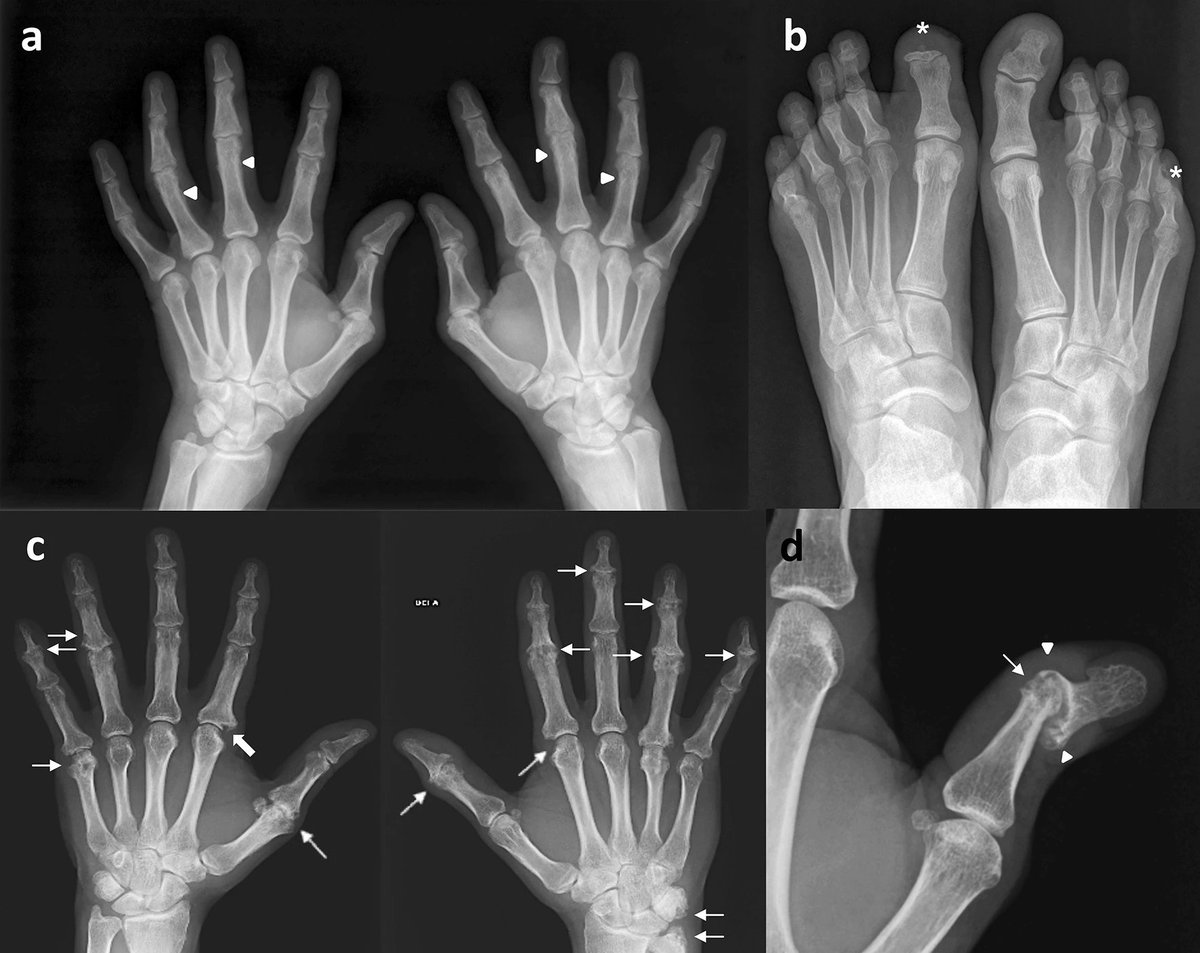

πŸ‘‰ characteristic patter of PsA is the coexistence of erosive changes and new bone formation as in this example where the same patient

πŸ‘‰(a, b) presented with fluffy periotitis in the proximal phalanges in both hands (arrow head)

πŸ‘‰ acro-osteolysis (*) in the distal phalanges of the first toe in the right foot and the fifth toe of the left foot

πŸ‘‰c.Polyarticular and asymmetrical PsA on hands with interphalangeal joints involved showing

πŸ‘‰articular space narrowing and erosions (thin arrows),

πŸ‘‰one of them is a Ξ© shaped erosion (thick arrow)

πŸ‘‰d

Subluxation and pencil-in-cup appereance in interphalangeal joint of the thumb in this particular case is another example of typical radiological changes in peripheral PsA.

Bony erosions narrowed the end of the proximal phalange as a β€œpencil” (thin arrows)

πŸ‘‰which rested in β€œcup” formed by the expanded base of the adjacent phalange (arrow head)